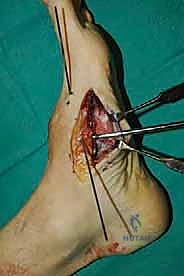

2. الشق الجراحي والوصول للمفاصل

يتم عمل شق جراحي واحد أو شقين (أحدهما في الجزء العلوي الداخلي والآخر في الجزء الخارجي) للوصول إلى مفاصل منتصف القدم دون الإضرار بالأوتار الحيوية والأعصاب والأوعية الدموية. يتم استخدام تقنيات الجراحة الدقيقة (Microsurgery) للحفاظ على الأنسجة المحيطة السليمة.

3. إزالة الغضاريف التالفة (Joint Preparation)

هذه هي الخطوة الأهم. يقوم الجراح بكحت وإزالة جميع الغضاريف المريضة والتالفة من بين العظام المراد دمجها. يجب الوصول إلى العظم الإسفنجي الصحي (Cancellous bone) الذي ينزف دماً، لأن هذا الدم يحتوي على الخلايا الجذعية وعوامل النمو الضرورية لعملية الالتحام (Fusion).